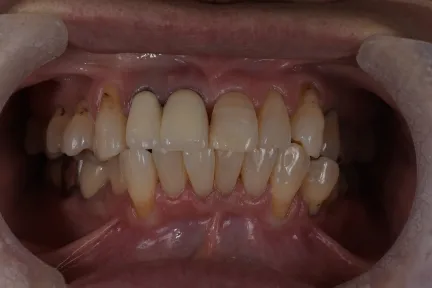

症例

case1

Before

After

施術内容 | 口腔内診査〜カウンセリング 歯周初期治療 仮歯を入れ機能的な評価 最終的な型取り〜装着 |

---|---|

治療期間 | 2ヶ月 |

治療回数 | 6回 |

リスク | クリーニングにこない場合歯茎が下がってくるため今後のメンテナンスが必須となる |

費用(税込) | 約¥341,000 |